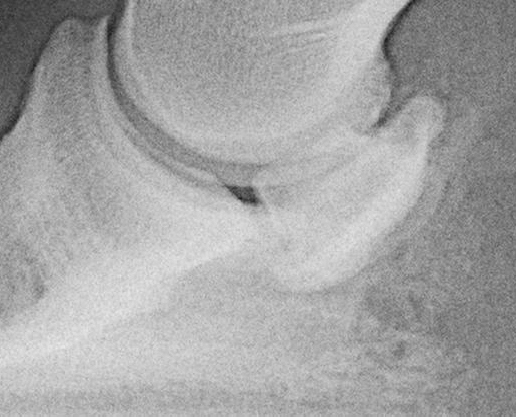

Deutliche Ausziehung am oberen Strahlbeinrand und Rauhigkeit im Anheftungsbereich der tiefen Beugesehne. Einziehung im Bereich der Gefäßkanäle.